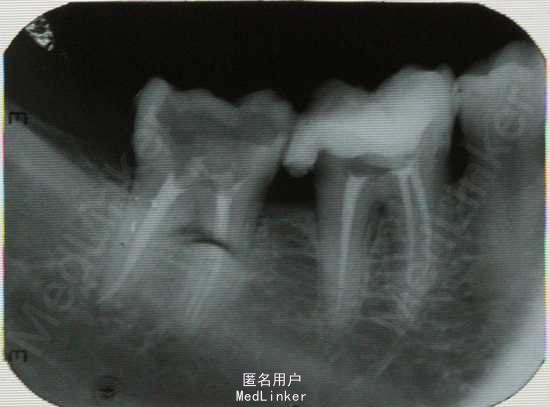

口内检查:见36,37牙冠大面积龋坏,进髓。扣++,冷+,探+。无明显松动,颊侧无瘘管。牙周状况一般。 牙片示:36,37深龋近髓,37远中根尖有明显暗影。

诊断:36慢性牙髓炎;37慢性根尖周炎。 处理:36,37根管治疗+纤维桩+冠修复

粗大根管常见于上颌前牙、上颌后牙腭根和下颌远中根。若扩挫清理不完善,很容易遗留管壁的感染物。另外,粗大根管可能同时伴随较大根尖孔,这就给根尖的严密充填增加了难度,容易使根尖密封不完全,从而导致症状不缓解或复发。